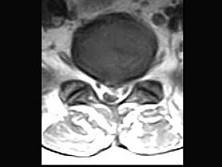

问题 男,50岁,有腰腿疼痛2个月,疼痛可向左下肢放射,请结合所提供图像,选出最佳选项 ( )

选项 A、L/S椎间盘膨出 B、L/L椎间盘膨出 C、L/L椎间盘突出 D、椎间盘变性 E、L/S椎间盘突出

答案 E